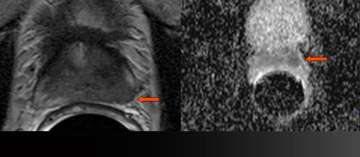

4) Example of Change to Nerve Sparing

- 59 year-old

- PSA 4.3

- standard biopsy: 3+3=6 but large volume left